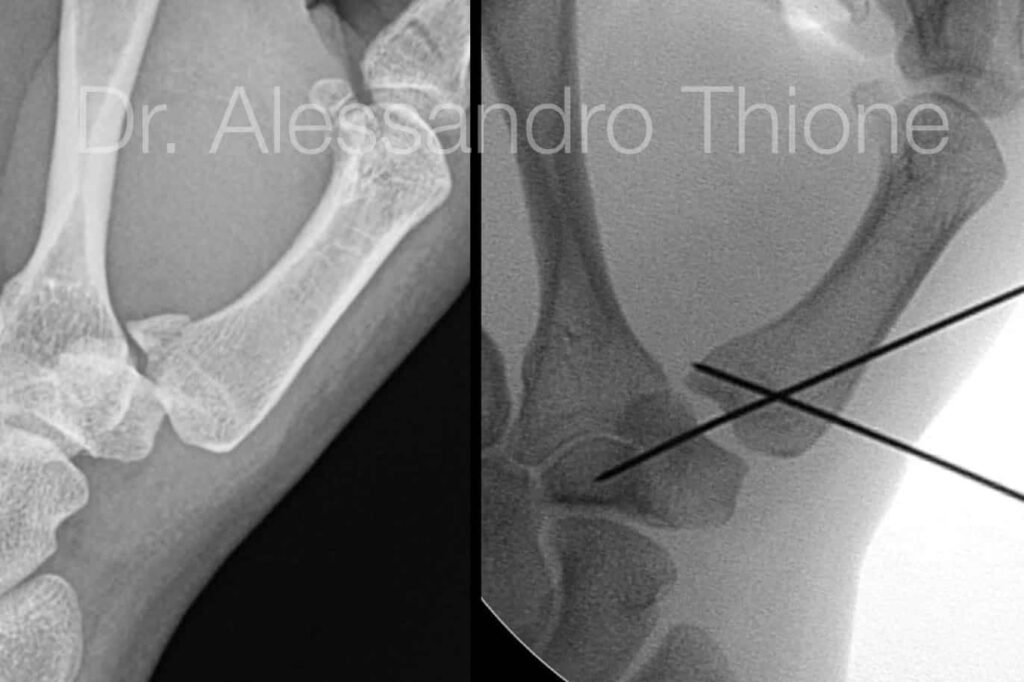

El diagnóstico de una fractura de Bennett generalmente se realiza mediante radiografías simples de la mano y el pulgar en diferentes proyecciones. Estas imágenes suelen ser suficientes para visualizar la fractura oblicua en la base del primer metacarpiano y la dislocación asociada de la articulación CMC. En la radiografía, se observa un pequeño fragmento triangular de hueso que permanece unido al ligamento oblicuo volar y que, debido a la acción de este ligamento y de los músculos, tiende a mantenerse en su posición anatómica respecto al trapecio, mientras que el resto del metacarpiano se desplaza proximal, dorsal y radialmente por la acción de los músculos abductor largo y extensor corto del pulgar.

2. Reducción Cerrada y Fijación Percutánea con Agujas de Kirschner

Este método es el más común para fracturas de Bennett desplazadas, pero que aún son reducibles mediante manipulación externa. Se realiza la reducción cerrada como se describió anteriormente y, una vez que los fragmentos están alineados, se insertan percutáneamente (a través de la piel, sin abrir la articulación) una o dos agujas de Kirschner finas. Una aguja suele dirigirse desde la base del metacarpiano hacia el fragmento pequeño para fijarlo en su posición. Otra aguja puede usarse para estabilizar el metacarpiano principal, fijándolo al hueso trapecio o al segundo metacarpiano adyacente para evitar su desplazamiento.

Las agujas sobresalen de la piel y se cubren para evitar infecciones. Se mantiene una inmovilización con férula o yeso durante el tiempo que las agujas permanecen en su lugar, que suele ser de aproximadamente 4 semanas. Pasado este tiempo, se retiran las agujas en consulta y se inicia el programa de rehabilitación. Este método ofrece una mayor estabilidad que el yeso solo, pero aún presenta un riesgo de desplazamiento si la fijación no es lo suficientemente sólida o si el paciente no sigue las precauciones.

Este enfoque quirúrgico se reserva generalmente para fracturas de Bennett con un desplazamiento significativo (típicamente > 3 mm), cuando la fractura no puede ser reducida de forma cerrada, o si hay un fragmento articular grande e inestable. La técnica implica realizar una incisión quirúrgica para exponer la articulación y la fractura bajo visión directa. Los fragmentos óseos se manipulan y se alinean de forma precisa (reducción anatómica) y luego se fijan internamente. La fijación puede realizarse con agujas de Kirschner, tornillos pequeños o, en casos complejos, miniplacas y tornillos. La elección del implante depende del tamaño y patrón de la fractura.